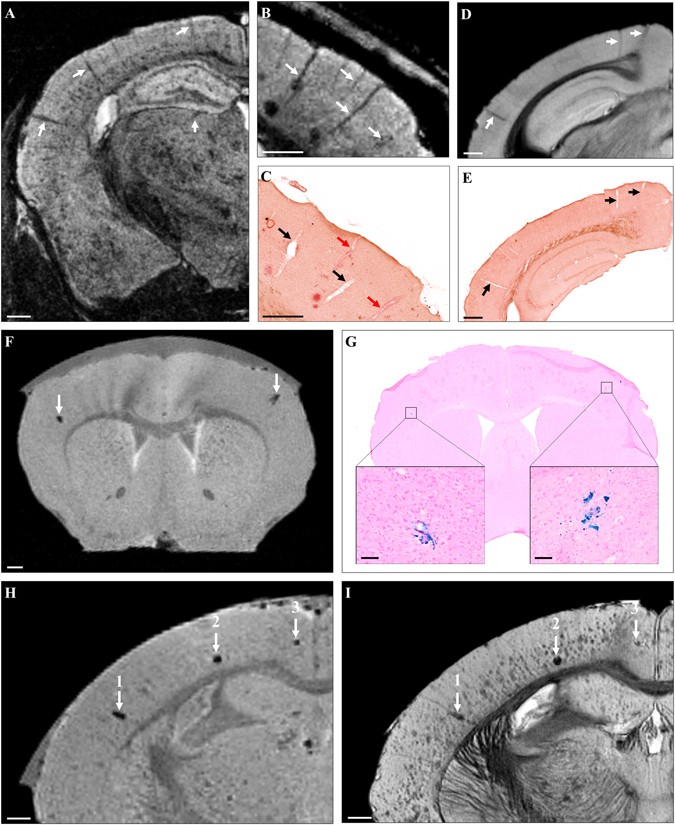

Figure 7

Visualization of CAA and cerebral microhemorrhages by Gd-stained MRI. Linear hypointense elements corresponding to blood vessels were detected on MR images of mouse models of amyloidosis (A–C, arrows). Registration between MR images (B) and histological sections (C) showed that some blood vessels seen on MRI were matched with CAA-positive vessels (red arrows) while some others were matched with CAA-negative vessels (black arrows). MR images of C57Bl/6 amyloid-free mice showed similar hypointensities (D, arrows) that were matched with blood vessels (E, arrows) confirming that CAA was not responsible of the hypointense nature of blood vessels by Gd-stained MRI. Sparse focal signal attenuations were observed on MR images before Gd-staining (F). They could be registered with microhemorrhages on Perls’ stained histological sections (G, boxes). Microhemorrhages easily seen on MRI before Gd-staining (H, arrows) could be matched with some hypointense spots on Gd-stained MRI (I, arrows). Large microhemorrhages (1, 2) were easily distinguished from amyloid plaques on MR images but small microbleeds (3) and amyloid plaques were similar in appearance. Scale bars: 500 µm (A–F,H,I) and 100 µm (G).